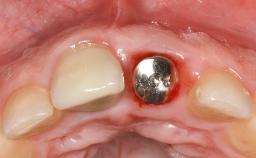

Reconstructive Surgical Treatment of Peri-Implantitis with Long-Term Follow-up

A 72-year-old female patient was referred to the specialist clinic with signs of peri-implantitis associated with implant 14. Two implants (sites 14 and 15) had been in function for three years. The patient was in good general health and was not taking any medication. She was a former smoker (12–15 cigarettes a day for 50 years) but had ceased smoking two years prior to implant placement. Her periodontal condition was stable, with no probing depths above 5 mm and a full-mouth plaque score (FMPS) of 35%.